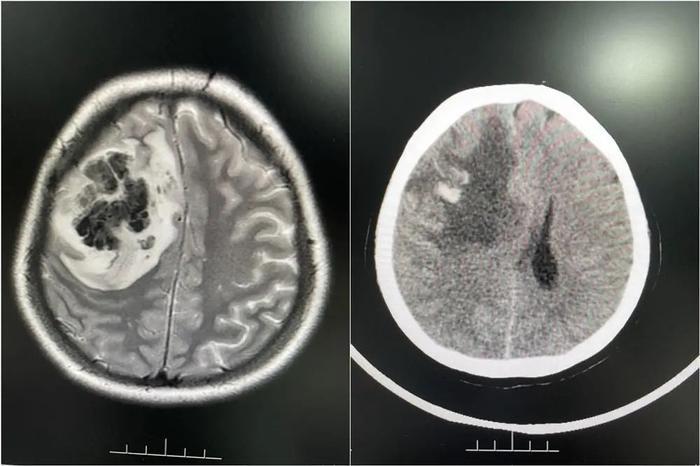

影像检查提示婷婷右侧额叶占位性病变合并出血

随后婷婷在当地医院查出右侧额叶占位性病变合并出血,医生怀疑是脑肿瘤卒中。陈女士说:“婷婷当时已经昏迷不醒,都剃了头发准备手术。”为寻求进一步诊疗,2月底,家人陪同婷婷来到广东三九脑科医院。

医院接诊医生仔细分析后,发现婷婷颅内病变不是脑肿瘤。结合病史和相关影像资料,该院神经内一科副主任匡祖颖初步怀疑是颅内静脉窦血栓。进一步完善全脑血管造影,证实是颅内静脉窦血栓形成合并出血。